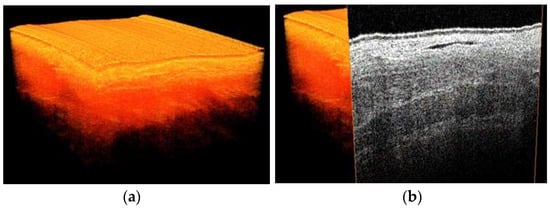

3D images were obtained at four locations of the gastric tube (Figure 5). On the 3D scans, different tissue layers could be distinguished. By comparison with histopathology slides, these layers could be identified. Importantly, the localization of the blood vessels of the reconstructed gastric tube was similar in OCT images compared to histopathology (Figure 6). Furthermore, because lymph fluid is a low-scattering medium, lymph vessels could be identified in the OCT images as well.

Figure 5.

3D OCT scan of the gastric tube, (a) volumetric representation (b) with cross section visualized.